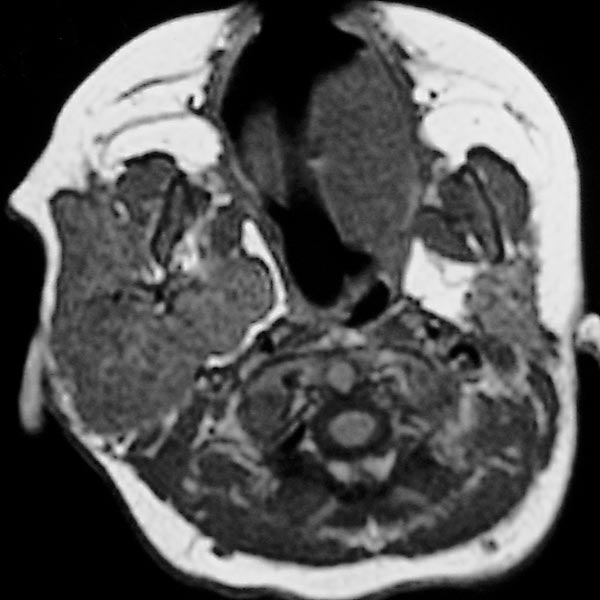

Transverse T1-weighted, non-enhanced MRI of the upper neck shows the tumor to be subcutaneously located, clearly solid, and sharply demarcated from surrounding tissue. The girl is now 12 months old, and the tumor has not regressed.

Transverse, T2-weighted, fat-saturated MRI of the upper neck again shows the subcutaneously located tumor very clearly as a hyperintense, sharply demarcated mass with central flow voids as a sign of intense arterial perfusion. Typical image of a subcutaneously located infantile hemangioma.